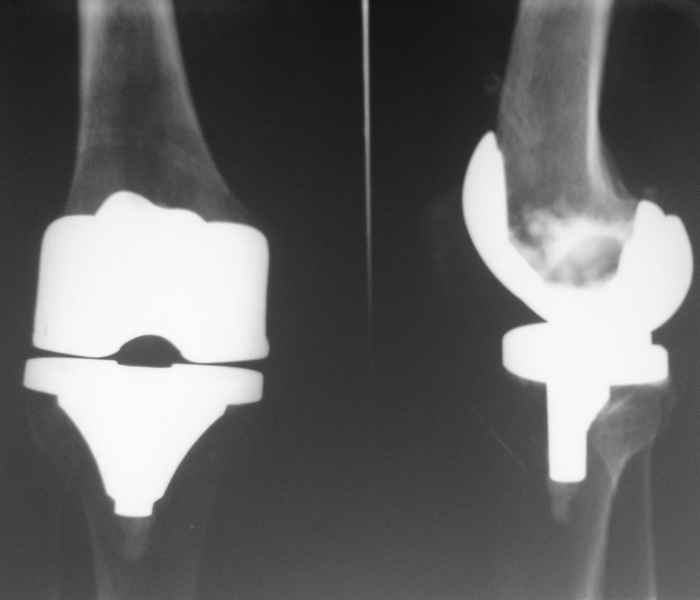

В июле 2007 года выполнена ревизия - полости сустава нет. Капсула сустава имеет толщину от 1 до 1.5 см, собственная связка надколенника имеет толщину до 3 см. Сустав заполнен фиброзно-рубцовой тканью. Компоненты стабильны.

Резецирована капсула, удалены фиброзные ткани из сустава. В области межмыщелковой ямки на бедре обнаружены 2 канала уходящих в мыщелки и проксимально, глубиной до 2 см и диаметром до 1 см. Выскаблены и заполнены синтетическим костным трансплантатом с ванкомицином.Взяты ткани из разных отделов сустава для бак. исследования.

Есть вопросы к установке протеза. Скорее всего тибиальное плато было не конца резецировано и в задненаружных отделах осталась ступенька. Это привело к тому, что тибиальный компонент завалился на варус.

По представленным снимкам (patella infera) и по клиническому описанию у Вашего больного типичный Артрофиброз (Knee Arthrofibrosis) обычное после замены сустава осложнение, характеризуется ограничением движения в суставе за счет образования рубцовой ткани. Такое осложнение встречается и после травм коленного сустава или после восстановительных работ на передней крестообразной связке.

Тип 4 сгибание меньше 30, разгибание меньше 10 +Patalle infera